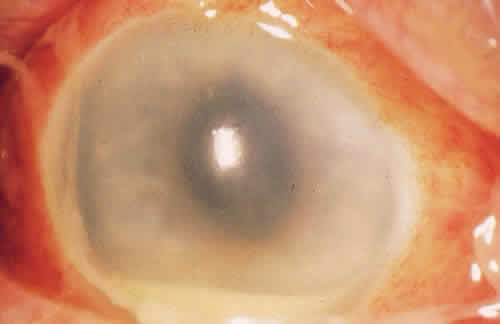

For the factors of innate immunity to be available at the site of potential infection, the factors must be brought to the area of interest through the bloodstream. The acute inflammatory response to bacteria or tissue injury is characterized by capillary dilation and increased capillary permeability. This transfers to the conjunctival epithelium the neutrophils, which play a crucial role in the defense against pyogenic bacteria, such as pneumococci and streptococci. In addition to furthering the transfer of leukocytes, the increased capillary permeability brings about a massive transudation of bactericidal factors contained in the serum: C-reactive protein, defensins, properdin, and the complement system (Fig. 1). These factors aid in the adherence of bacteria to the polymorphonuclear leukocyte and ultimately in phagocytosis.2 Defensins, for example, are considered to be one of the earliest peptide effectors of innate immunity.15 They are released by neutrophils and are present in tears and in the ocular mucosa.16 Defensins have antimicrobial activity against gram-positive and gram-negative bacteria, fungi, and viruses and accelerate wound healing by their mitogenic effect on epithelial cells and fibroblasts.